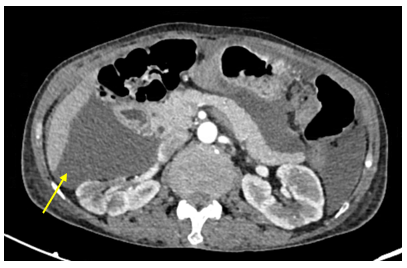

Chụp CT ổ bụng có tiêm thuốc cản quang:

Hình 1: Hình ảnh khối vùng tiểu khung kích thước 52x69mm (vòng tròn đỏ).

Hình 3: Dịch tự do ổ bụng, chỗ dày nhất 53 mm (mũi tên vàng).

Chụp CT lồng ngực: